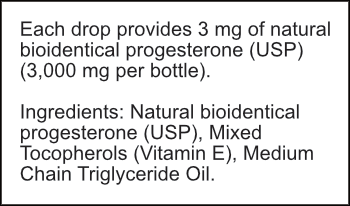

Our bio-identical progesterone is designed and formulated like no other. Unlike progesterone creams that are typically low concentration or contain thyroid suppressive oils, or progesterone pills / tablets that are largely inactivated by your liver, or suppositories that are prone to crystallization and can’t be absorbed… Progesterone Oil solves all of these problems. It’s highly concentrated at more than 10% progesterone, doesn’t crystalize, and contains a special solution allowing for close to 100% absorption. The secret lies in the special formulation with Vitamin E, which acts as a carrier to deliver the progesterone directly into the bloodstream. This makes it the quickest and most absorbable bio-identical progesterone source available.

Our Progesterone Oil contains 1 fl. oz. / 30 ml (over 3,000 mg per bottle) of pure, bio-identical progesterone, with high-quality Vitamin E, and pure non-GMO MCT oil (Coconut oil).